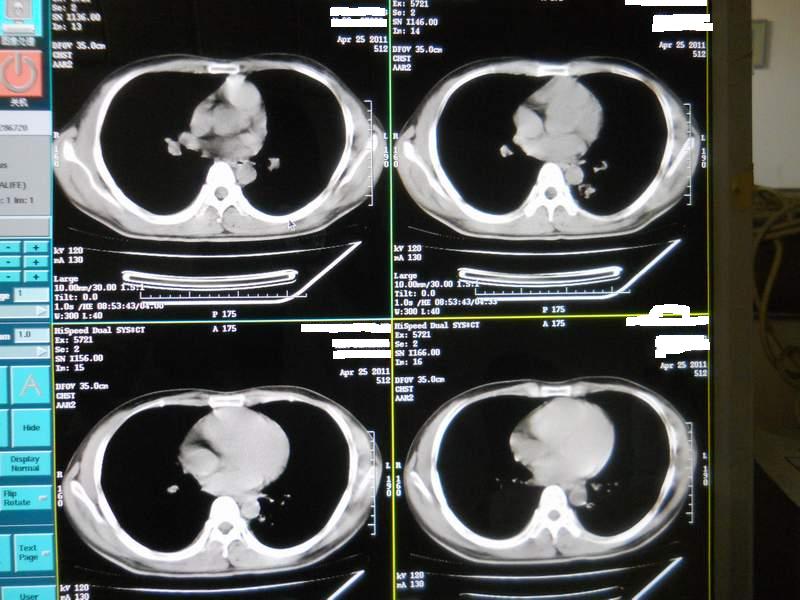

肺霉菌感染

男,22岁,一年前诊断马尔菲尼青霉菌感染,多次复查CT。多次HIV阴性。最近两次CT图片。有实验室结果。

最近实验室检查结果:霉菌感染。